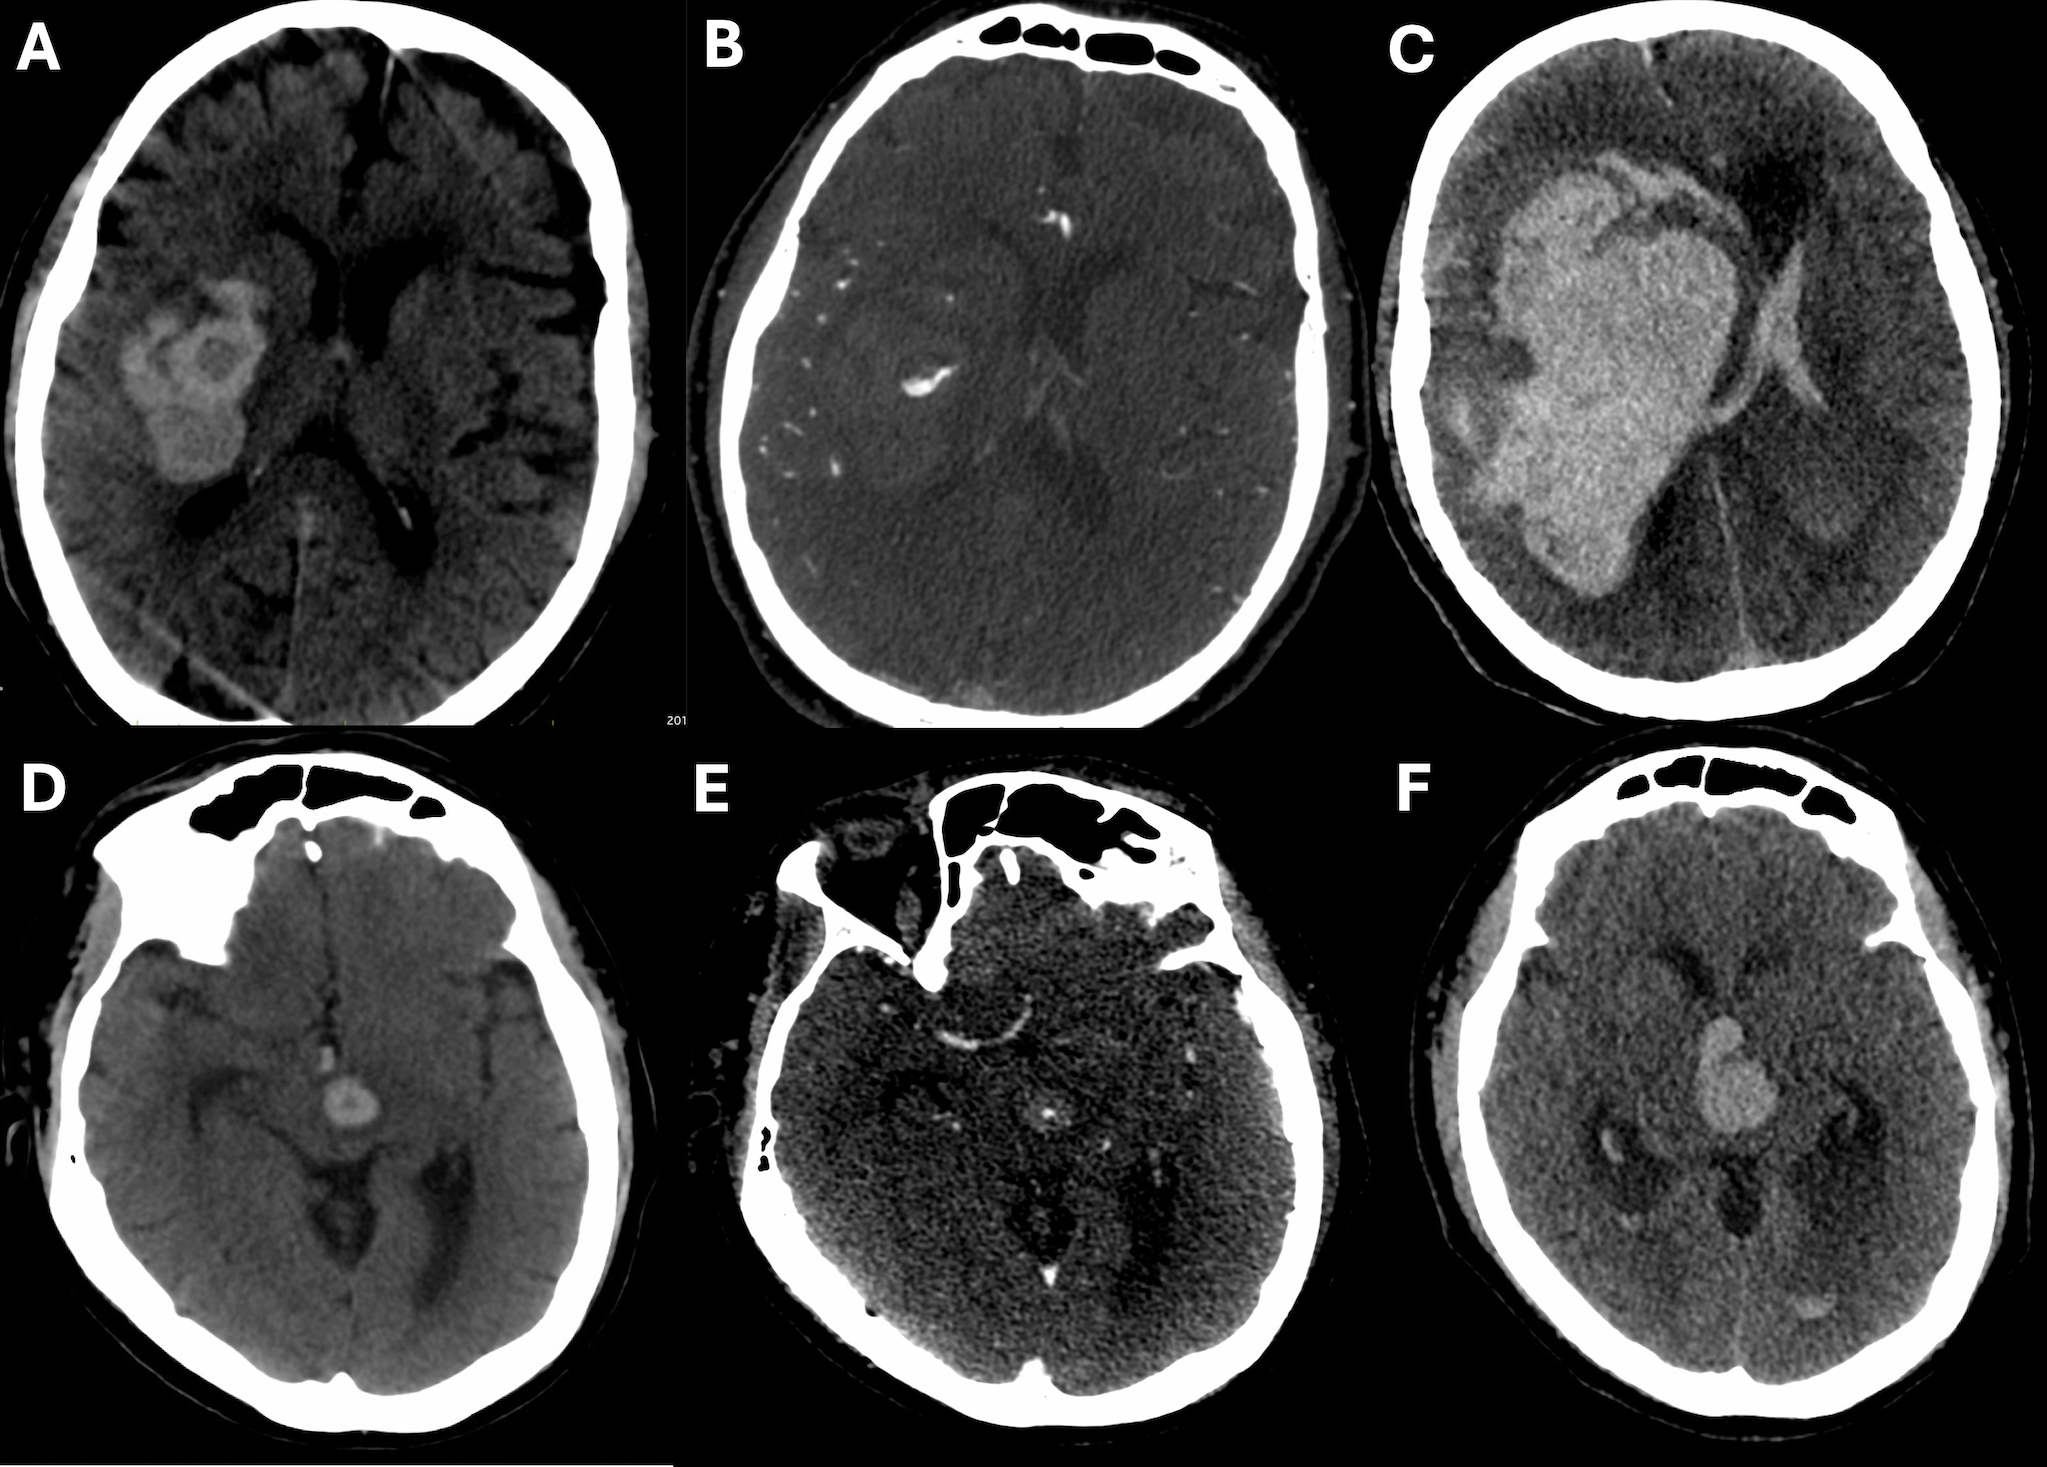

Methods: We analyzed 200 consecutive acute ICH patients admitted at Foothills Medical Centre in Calgary, Canada (development cohort) and analyzed 304 patients from the multicenter observational study PREDICT (validation cohort). The Black-&-White (B&W) sign was defined as any visually identified spot sign on CTA co-localized with a hypodensity sign on the corresponding NCCT (Figure 1). The primary outcome was hematoma expansion (≥6mL or ≥33%). Secondary outcomes included absolute (<3mL, 3-6mL, 6-12mL, ≥12mL) and relative (0%, <25%, 25-50%, 50-75%, or >75%) hematoma growth scales.

Results: In the development cohort, 22% (n=44) showed the spot sign, 34.5% (n=69) the hypodensity sign, and 7% (n=14) the B&W sign. Those with the B&W sign had higher proportions of HE (100% vs. 19.4%, p<0.001), greater absolute hematoma growth (23.37 mL [IQR=15.41-30.27] vs. 0 mL [IQR=0-2.39], p<0.001) and relative hematoma growth (120% [IQR=49-192] vs. 0% [0-15%], p<0.001) in comparison to those without. The B&W sign yielded a specificity of 100%, a PPV of 100%, and an accuracy of 82%.

In the validation cohort, 25% (n=76) showed the spot sign, 39.1% (n=119) the hypodensity sign, and 9.5% (n=29) the B&W sign. Those with B&W signs had higher proportions of HE (79.3% vs. 30.2%, p<0.001), greater absolute hematoma growth (19.1 mL [IQR=6.4-40] vs. 0.8 mL [0-5.6], p<0.001), and relative hematoma growth (92% [IQR=16-151%] vs. 9% [0-34%], p<0.001) in comparison to those without. The B&W sign yielded a specificity of 97%, a PPV of 79%, and an accuracy of 71%. We found a consistent progressive improvement in predicting HE when hypodensity and spot signs are absent, individually present, both present but not co-localized, and co-localized (Figures 2-3). The inter-rater agreement was excellent (k=0.84) in the development cohort, with a uniform imaging protocol of NCCT immediately followed by CTA at a single center, and moderate (k=0.54) in the validation cohort at multiple centers.